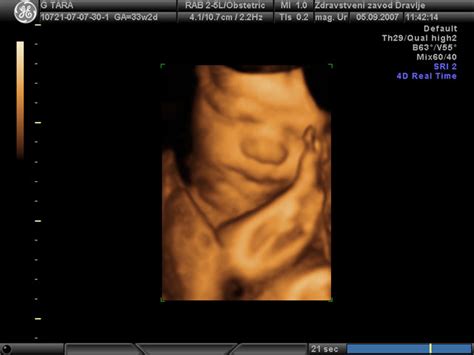

Preden se poglobimo v znake odtekanja, je dobro razumeti, kaj plodovnica sploh je. Predstavljajte si jo kot otrokovo prvo zasebno stanovanje - varno, toplo in udobno zavetje, kjer preživi devet mesecev. Plodovnica je veliko več kot le mehurček vode. Njena vloga za otrokov razvoj je ključna:

Na začetku nosečnosti je plodovnica sestavljena predvsem iz vode, ki jo proizvaja vaše telo. Kasneje, ko se otroku razvijejo ledvice, pa začne pomemben del tekočine predstavljati njegov urin. Sliši se morda malce nenavadno, vendar je to popolnoma naraven in zdrav proces. Plod v maternici namreč urinira skoraj vsakih deset minut. Otrok zaužije skoraj liter plodovnice na dan, zaradi česar je izločanje urina povsem naravno. Večina amnijske tekočine, kot imenujemo plodovnico, sestavlja torej plodov urin, ki pa seveda ni takšen, kot ga poznamo mi. Seveda pa plod ne preživi vseh tednov v isti amnijski tekočini. Plodovnica se namreč vsake tri ure popolnoma obnovi. Ta tekočina ščiti plod pred zunanjimi vplivi, blaži prenos sil ob morebitnih udarcih v trebuh in pomaga pri ohranjanju stalne telesne temperature.